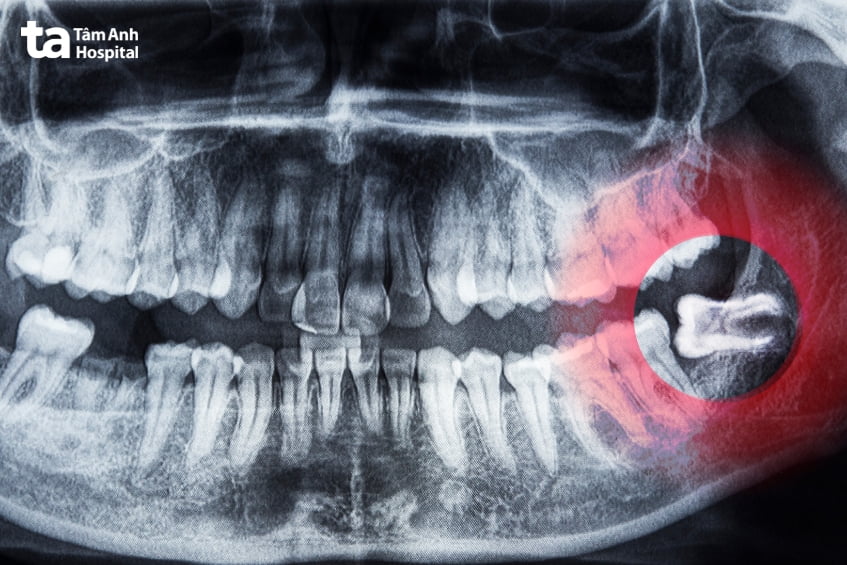

Chụp X-quang là phương pháp cần thiết để xác định hướng mọc, độ nghiêng và mức độ mọc ngầm của răng khôn, giúp bác sĩ phát hiện các tổn thương ở răng kế cận, tình trạng tiêu xương hoặc hình thành ổ áp xe (nếu có).